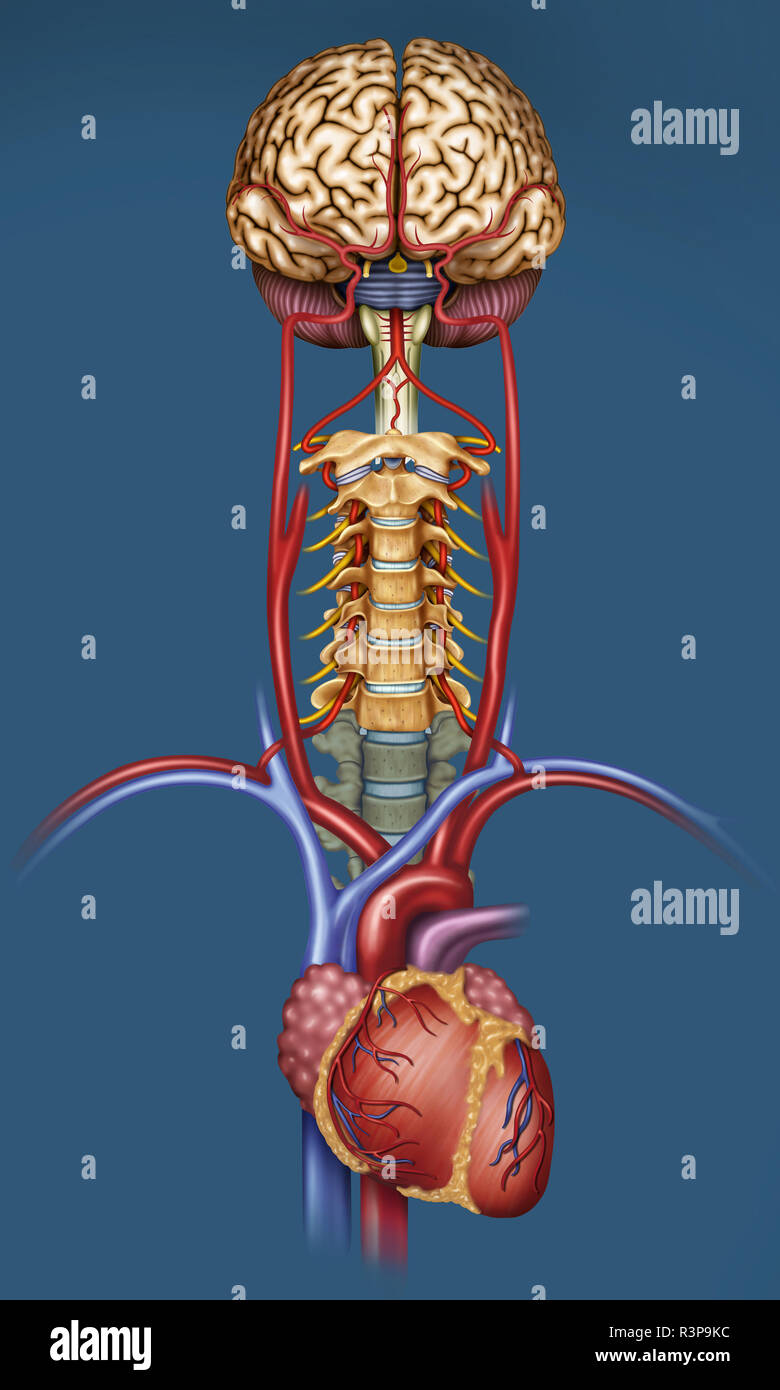

RFR3P9KW–Illustration der Blutversorgung des Gehirns. Das Gehirn hat wenig Kapazität, Nährstoffe zu speichern, aber es braucht eine hohe Versorgung mit Sauerstoff und Glukose.

RFR3P9KC–Illustration der Blutversorgung des Gehirns. Das Gehirn hat wenig Kapazität, Nährstoffe zu speichern, und benötigt eine hohe Versorgung mit Sauerstoff und Glukose.